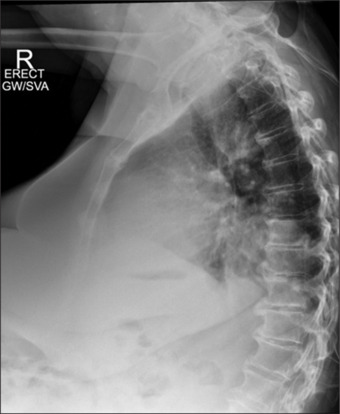

纵隔肿块:急诊诊断困境。

Mediastinal mass: Diagnostic dilemma on acute medical take.